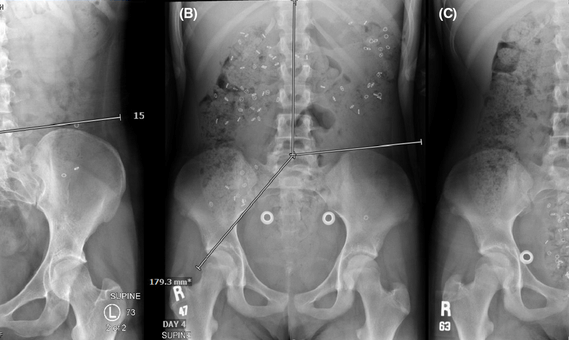

In some cases, we may use a radiopaque marker test or wireless motility capsule to measure how quickly stool moves through your colon.